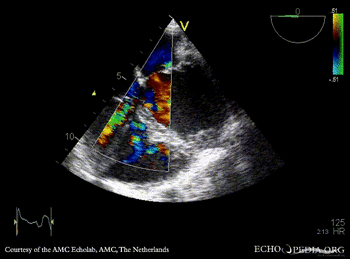

| Muscular VSD

| PSAX: muscular VSD